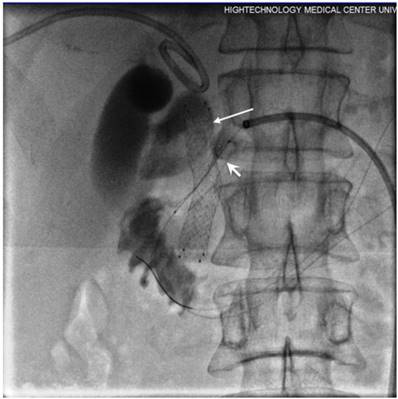

Figure 1

Inoperable pancreatic head cancer presented with jaundice and PD dilation. Biliary external-internal (long arrow) and PD drainage (short arrow) performed.